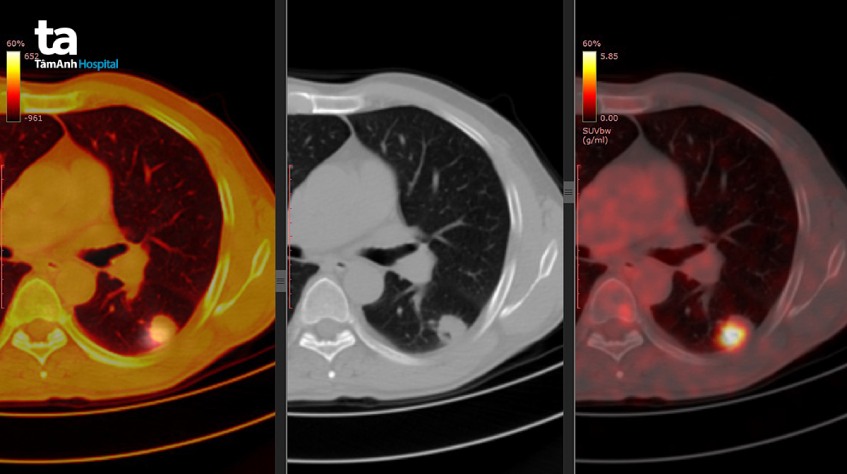

Bằng việc đưa vào tĩnh mạch một chất chỉ điểm phóng xạ, hoạt chất này xuất hiện ở những khối u hoặc vị trí đang có quá trình viêm. Quá trình nhiễu xạ của hoạt chất này được buồng thu tín hiệu của máy CT PET ghi nhận lại và tái tạo thành hình ảnh. Hiện nay loại chất thường được sử dụng nhất là FDG, một loại chất có cấu trúc giống với phân tử đường glucose (nguồn dinh dưỡng chính của các tế bào). Thông qua định vị và định lượng hợp chất này, các chuyên gia dễ dàng tìm được các ổ viêm hoặc những tế bào ung thư di căn đến những nơi khó phát hiện nhất.(1)

Tế bào nào cũng sử dụng đường glucose để tạo ra năng lượng. Điều này cũng đúng ở tế bào ung thư. Tuy nhiên, với tốc độ phát triển cực nhanh của tế bào ung thư, chúng “háu ăn” đường glucose hơn tất cả các tế bào khác trong cơ thể. Chính vì thế việc đưa một chất chỉ điểm phóng xạ có cấu trúc giống glucose, như FDG (18-fluorodeoxyglucose), sẽ nhạy với các tế bào ung thư này. Từ đó chỉ điểm cho các bác sĩ biết các dòng tế bào nguy hiểm này đang ở đâu để chuẩn bị kế hoạch điều trị phù hợp. (3)

Về mặt chức năng, kỹ thuật CT chỉ cho bác sĩ thấy về mặt cấu trúc các cơ quan trong cơ thể, qua đó cũng có thể quan sát được khối u khi chúng ở một kích thước nhất định. Trái lại PET CT có thể thấy những khối u ở kích thước nhỏ hơn, các nốt di căn xa mà kỹ thuật CT không phát hiện. Đồng thời việc định lượng mật độ của chất chỉ điểm còn cho phép gợi ý một khối u là lành hay ác.